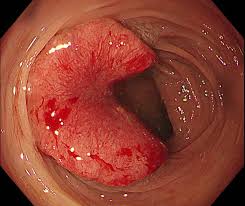

(2) 혈변 또는 점액변

대장암의 주요 증상 중 하나는 대변에 피가 섞여 나오는 것입니다.

① 선홍색 또는 검붉은 피

직장 쪽 암일수록 선홍색 출혈이, 결장 쪽 암일수록 검붉은 색의 혈변이 나타날 수 있습니다. 단순 치핵(치질)과 혼동되기 쉬우므로 반복되거나 장기적으로 나타나는 경우 반드시 검사를 받아야 합니다.